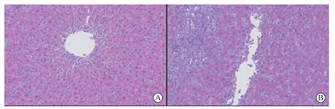

B1、C1组受鼠根据GW/RLW分组,组间GW/RLW差异亦具有显著统计学意义(P<0.01,表1)。移植肝脏在术后的第7天被取出,并行HE染色行组织学分析。两组均可以观察到肝窦扩张,肝窦内门静脉区有较多的淋巴细胞浸润,血管内皮也可见淋巴细胞浸润,提示移植排斥反应的发生,B1、C1组Banff RAI评分分别为8.5±0.5和7.5±0.8,组间差异未见统计学意义(P>0.05,表3,图4),可能是由于均处于急性排斥反应病理变化的早期。

C1组CD3 mRNA水平在术后第7天也较术后48 h显著上调,由0.05±0.07升高至18.7±20.0(P<0.05);但在B1组术后48 h和术后第7天的CD3 mRNA分别0.12±0.23和0.40±0.70,差异无统计学意义(P>0.05)。术后第7天,C1组CD3的mRNA水平为18.7±20,显著高于B1组的0.05±0.07(P<0.05)。提示C1组受鼠移植肝有更多的CD3+T淋巴细胞浸润(图4、图8)。并且在术后第7天C1组的细胞表面共刺激分子B7-H1的mRNA水平为6.5±0.7,低于B1组的7.8±0.9(P<0.05),提示C1组的维持免疫接受的共刺激分子B7-H1被降低(图9)。